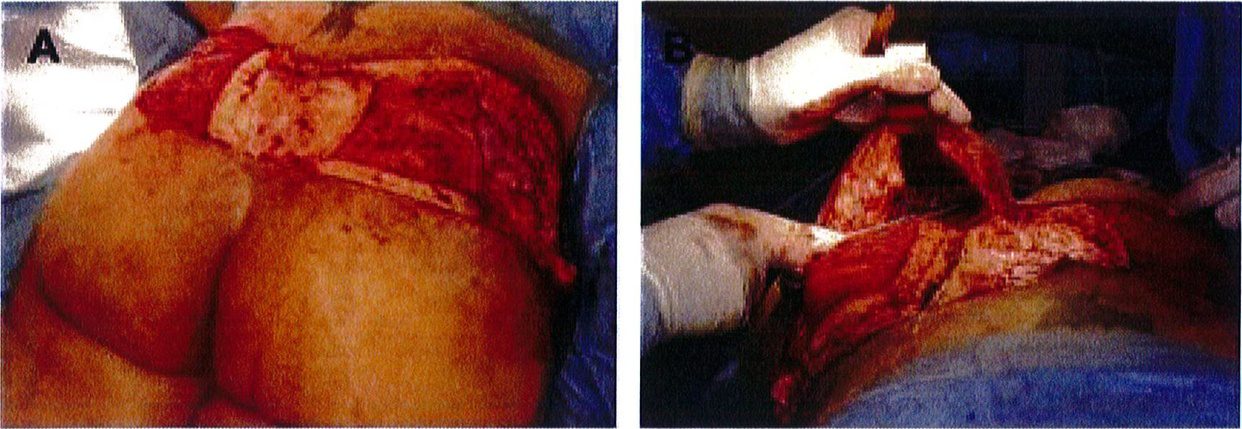

Phần da phía trên mông hình chêm đã đánh dấu trước đó được rạch ra, để lại lớp mỡ trên mặt sau xương cùng nhằm dẫn lưu bạch huyết. Vạt mông sẽ được đánh dấu vị trí sau khi đã rạch hai đường trên dưới, sau đó được khử biểu mô (hình 1D, 2A).

BIẾN CHỨNG VÀ QUẢN LÝ BIẾN CHỨNG

Vạt sẽ được bóc tách thẳng từ trên xuống lớp cân nông bằng các dụng cụ bóc tách sao cho đường bóc ở mặt trên, trong và ngoài thẳng góc với khối cơ ở dưới. Mặt dưới sẽ được bóc tách với một góc nghiêng (thay vì góc vuông như 3 mặt còn lại) cho tới lớp cân nông. Một túi bao được thiết kế để bọc phần vạt lại, ngay phía trên cân cơ mông lớn (Hình 2B) (Pocket for the flap ở hình 2A). Lớp cân ở mặt trên, trong và ngoài được chia tách nhau ra, sau đó tách một phần cơ mông lớn (chiều dài khoảng 5-6cm) ra đi cùng với phần tố chức dưới da đã được khử biểu mô trước đó, rồi thực hiện thao tác lật vạt lên trên (Hình 3).

Bằng cách tách đôi khối co mông lớn, tạo thuận cho việc lật vạt từ nửa dưới lên trên, đồng thời bảo tồn tối đa mạch cấp máu cho vạt so với các loại vạt khác (Bảng 1). Không ghi nhận trường hợp nào bị hoại tử toàn bộ vạt hoặc hoại tủ mỡ. Các tác giả không ghi nhận bất kỳ trường hợp xuất hiện khối máu tụ hoặc bướu huyết thanh nào sau phẫu thuật. Điều này có thể do sự đóng góp của một số yếu tố, bao gồm việc bảo tồn được hệ bạch huyết sau xương cùng, giảm thiểu các khoang tôn dư, băng ép sau phẫu thuật và sử dụng dẫn lưu. Cho đến nay, chỉ có 1 bệnh nhân phải điều trị chỉnh sửa lại vạt sau phẫu thuật.

Vạt được lật lên trên và bờ tự do của chúng được khâu nối vào 208

túi bao đã đặt trước đó bằng chỉ Quill 3-0 (chỉ khâu lớp cân nông với túi, không khâu cơ) (Hình 4).